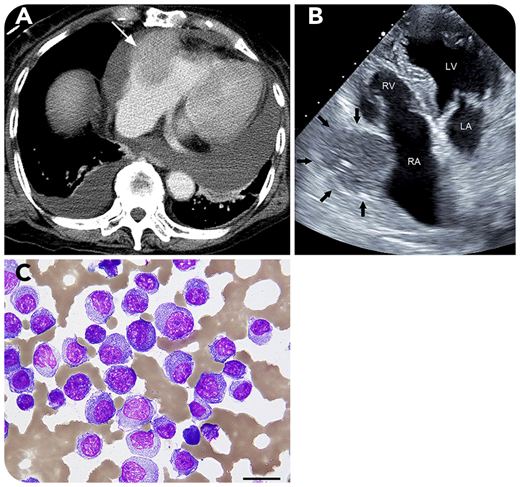

A 79-year-old woman visited our hospital because of back pain. Laboratory examination showed monoclonal λ light chains in the serum, and a population of 60% CD138+ plasma cells was found on bone marrow biopsy. Karyotype was normal, and whole-body computed tomography (CT) found no extramedullary lesions. She was diagnosed with immunoglobulin A λ-type multiple myeloma (MM), classified as stage 2 according to the Revised International Staging System; she started treatment with bortezomib plus dexamethasone and achieved complete response. One year later, multiple tumors in her right mammary gland were detected on CT. Mammary gland biopsy found plasmacytoma, resulting in a diagnosis of extramedullary lesions in MM. Four years after first visit, she was admitted with heart failure. Contrast-enhanced CT (panel A) and echocardiography (panel B; LA, left atrium; LV, left ventricle; RA, right atrium; RV, right ventricle) revealed a moderate amount of pericardial effusion and a mass (3.8 × 4.5 cm) in the right atrial wall (white arrow in panel A and black arrows in panel B) consistent with cardiac tamponade; pericardial drainage was then performed. Cytology for the bloody pericardial effusion showed clusters of plasma cells (panel C; periodic acid Schiff stain; original magnification ×400), indicating an extramedullary lesion to the pericardium. Fluorescence in situ hybridization from the bone marrow detected no cytogenetic abnormality. Although daratumumab, carfilzomib, and pomalidomide were administered, the mass enlarged, and she died thereafter.

Extramedullary lesions of MM mostly occur near the axial skeleton by direct infiltration from the bone marrow. However, cardiac lesions are rare.